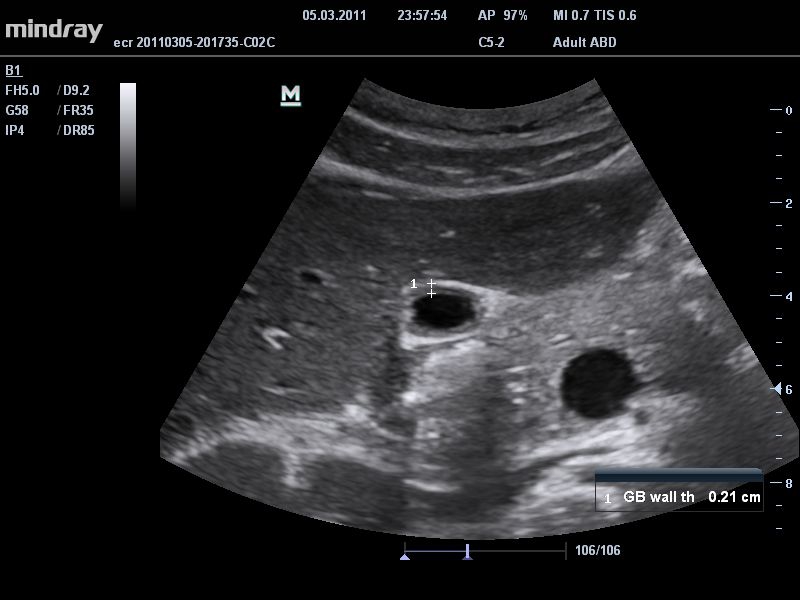

• THI со сдвигом фазы: увеличивает четкость визуализации желчного и мочевого пузыря и повышает отношение сигнал-шум.

• Режимы сканирования: B/M/CFM/PDI/Направленный PDI/PW, HPRF, Тканевая гармоника, М- и цветной М-режим.